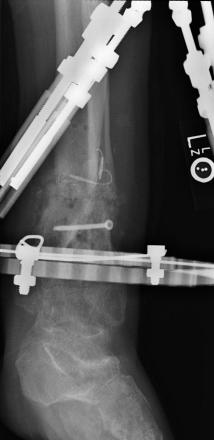

Postoperative (13th) images of left ankle

The image(s) displayed here were created following Liam's 13th surgery which was performed by Dr. Saunders. After a few hiccups getting

the surgery scheduled, Liam spent most of the September 13th afternoon in his 13th surgery. ;-) The surgery lasted about 5 hours and according

to the doctor, it was a good surgery. The 1st photo shows the new frame bracing that holds Liam's ankle together. The next series of photos show

various angles of the ankle and the rods that go from the frame into and through the left ankle. There was some concern that the swelling would

burst and allow for infection. Looks like we are now past that concern. Liam is still on antibiotics to ward of potential infection. The flesh

images show how the skin reacts to having the leg adjusted by the brace. The doctor has had to cut the skin to allow the rods to move freely.